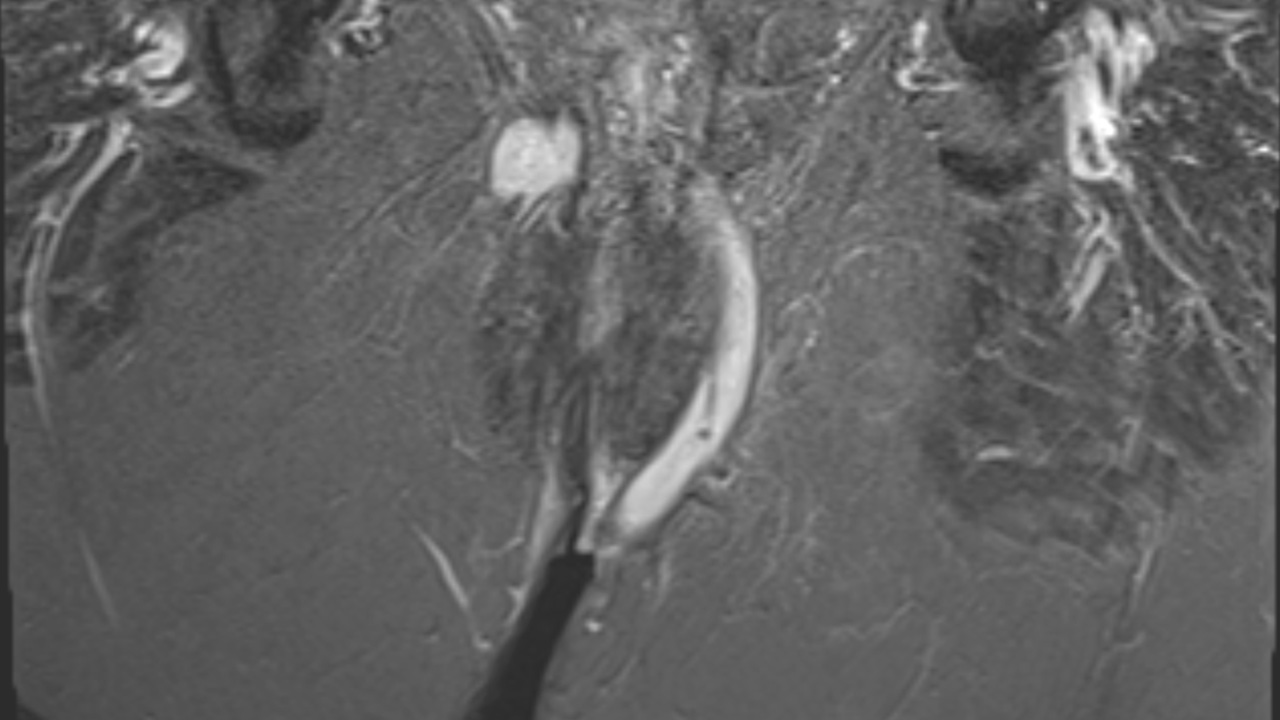

Virtual Examination Under Anaesthetic (vEUA) enables clinicians to build an anatomically representative model of the sphincters, levator plate, and fistula tracts from MRI in under two minutes.

vEUA provides a clear, interactive visualisation of complex disease, making it easier for surgeons and radiologists to plan procedures, share findings with colleagues, and communicate with patients.

Outside of surgical planning, the volumetry of the fistula tract and surrounding tissue (including length and branching of the tracts) can be measured with Entrolytics standard tooling.